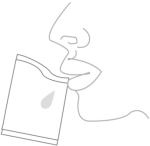

Figure 2 Methods for sputum sample collection

(2) Sputum specimen collection: After rinsing with water, cough up the sputum vigorously, put it into a specimen bag, and wipe the specimen with a disposable sterile cotton swab. (See Figure 2)